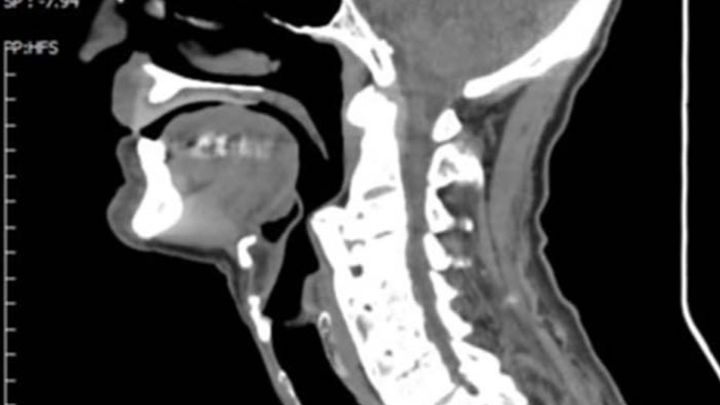

My name is Blaine and I am trying to raise funds for an old friend. He has had a form of arthritis in his neck for many years but it continues to get worse. The bone in his neck is slowly growing and closing off his esophagus and trachea (food pipe and windpipe). It is to the point now that he has extreme problem swallowing and breathing. He has lost 10 kg (from 55kg to 45kg) in the last two years and continuing to fail. He needs money in Thailand for corrective surgery. I have decided to take some steps to help him.